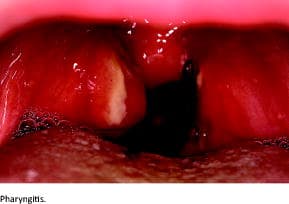

The median age at onset of symptoms was 33 months (interquartile range: 19-65 months). The mean duration of fever episodes was 4.45 days (95% confidence interval (CI): 3.92-4.98), and the mean duration of intervals between fever episodes was 29.66 days (95% CI: 25.31-34.01). Seasonal variation in the frequency of fever episodes was seen in 45.2% (14/31) of the patients. All patients had characteristic symptoms (pharyngitis, cervical adenitis and/or aphthous stomatitis) concomitantly with fever (Figure 1). Furthermore, 30 patients had other symptoms associated with the fever episodes, including headache, stomach ache, arthralgia, tiredness, rash, vomiting, diarrhoea or photophobia (Table 1). All patients were asymptomatic in the intervals between fever episodes. However, twelve patients experienced prodromal symptoms before fever episodes in the form of headache, fatigue or arthralgia.

Concomitantly with periodic fever, patients have at least one of the following characteristic symptoms: pharyngitis, aphthous stomatitis and/or cervical adenitis. As not all characteristic symptoms need to be present to make the PFAPA diagnosis, there will be variation in the patients’ clinical presentation. This becomes apparent when our findings are examined for the distribution of patients according to characteristic symptoms and are compared with the findings of other studies. Erythematous pharyngitis was present in 80.6% of the patients in our study, and exudative pharyngitis in 61.3%. Other studies have reported pharyngitis in 65-96% of patients [5, 7, 10, 12]. We found that 48.4% of our study population had aphthous stomatitis. In other studies, this was the case in 38-67% of patients [5, 7, 10, 12]. Lastly, 96.8% had cervical adenitis in our study, but this was only the case for 61-77% of patients in other studies [7, 10, 12].